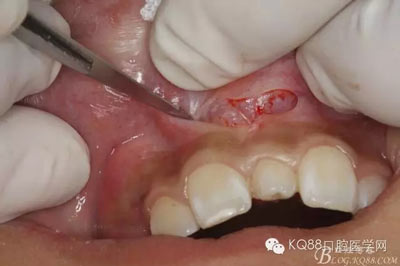

圖4.局部無痛浸潤麻醉下。行唇側弧形切口